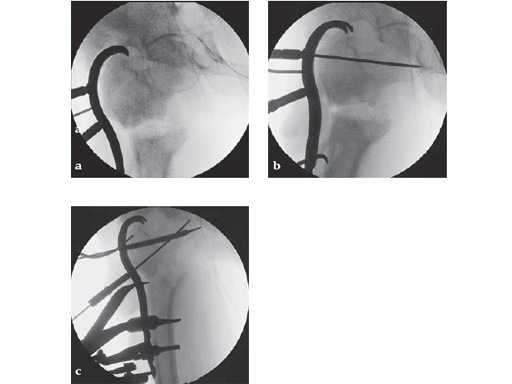

46-year-old female with an transverse intertrochanteric fracture

Case provided by Keith Mayo, Tacoma, USAHazards and labeling